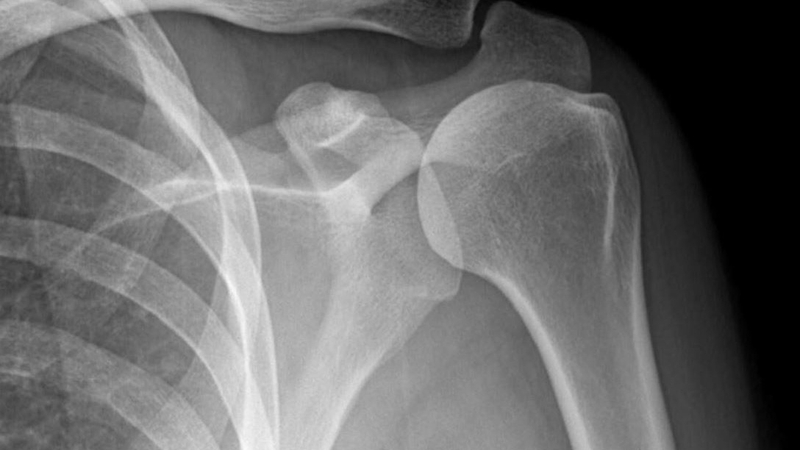

Chụp Xquang khớp vai đóng một vai trò quan trọng trong việc chẩn đoán các tình trạng vai khác nhau, từ gãy xương và trật khớp đến rách gân và các bệnh viêm nhiễm. Phát hiện và điều trị sớm là điều cần thiết để duy trì chức năng vai và ngăn ngừa các biến chứng lâu dài.

Chụp Xquang (X-quang) khớp vai là một công cụ chẩn đoán có giá trị được hưởng lợi rất nhiều từ những tiến bộ trong công nghệ kỹ thuật số. Quy trình này diễn ra nhanh chóng, hiệu quả và hạn chế tiếp xúc với bức xạ. Thông qua việc cung cấp hình ảnh rõ ràng và chi tiết về khớp vai, chụp Xquang đóng vai trò quan trọng trong chẩn đoán và điều trị các tình trạng vai khác nhau. Nếu bạn bị đau vai hoặc nghi ngờ chấn thương, hãy tham khảo ý kiến bác sĩ về việc chụp Xquang khớp vai để chẩn đoán chính xác và có kế hoạch điều trị hiệu quả.

Chụp Xquang khớp vai giúp chụp xương, khí, vật chất và mô mềm ở khớp vai trên mặt phẳng 2D. Kỹ thuật hình ảnh này cho phép bác sĩ phát hiện những bất thường và nếu cần thiết có thể sử dụng các kỹ thuật chuyên biệt bổ sung để chẩn đoán toàn diện. Tùy thuộc vào tình trạng thể chất của bệnh nhân, chụp Xquang có thể được chụp ở tư thế đứng hoặc nằm. Kỹ thuật viên thường chụp ảnh ở hai tư thế thẳng đứng và nghiêng. Toàn bộ quá trình quét chỉ kéo dài khoảng 10 - 20 giây.

Chụp Xquang khớp vai là một công cụ chẩn đoán quan trọng được sử dụng để xác định và điều trị các vấn đề về xương và khớp khác nhau ở vai. Đây thường là phương pháp đầu tiên được các bác sĩ sử dụng để kiểm tra, sàng lọc và phát hiện những bất thường ở khớp vai, giúp họ xác định kế hoạch điều trị phù hợp nhất cho từng bệnh nhân.

Chụp Xquang khớp vai rất cần thiết để chẩn đoán các tình trạng khác nhau ảnh hưởng đến khớp vai, từ đó đề xuất phương pháp điều trị thích hợp nhất.